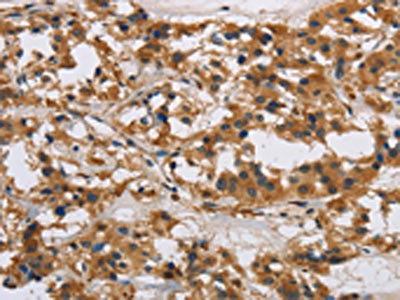

The image on the left is immunohistochemistry of paraffin-embedded Human thyroid cancer tissue using CSB-PA891383(IL17RB Antibody) at dilution 1/40, on the right is treated with synthetic peptide. (Original magnification: ×200)